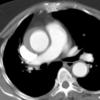

Gallery Aorta Dissection

Dissection

Ao Diss 1a